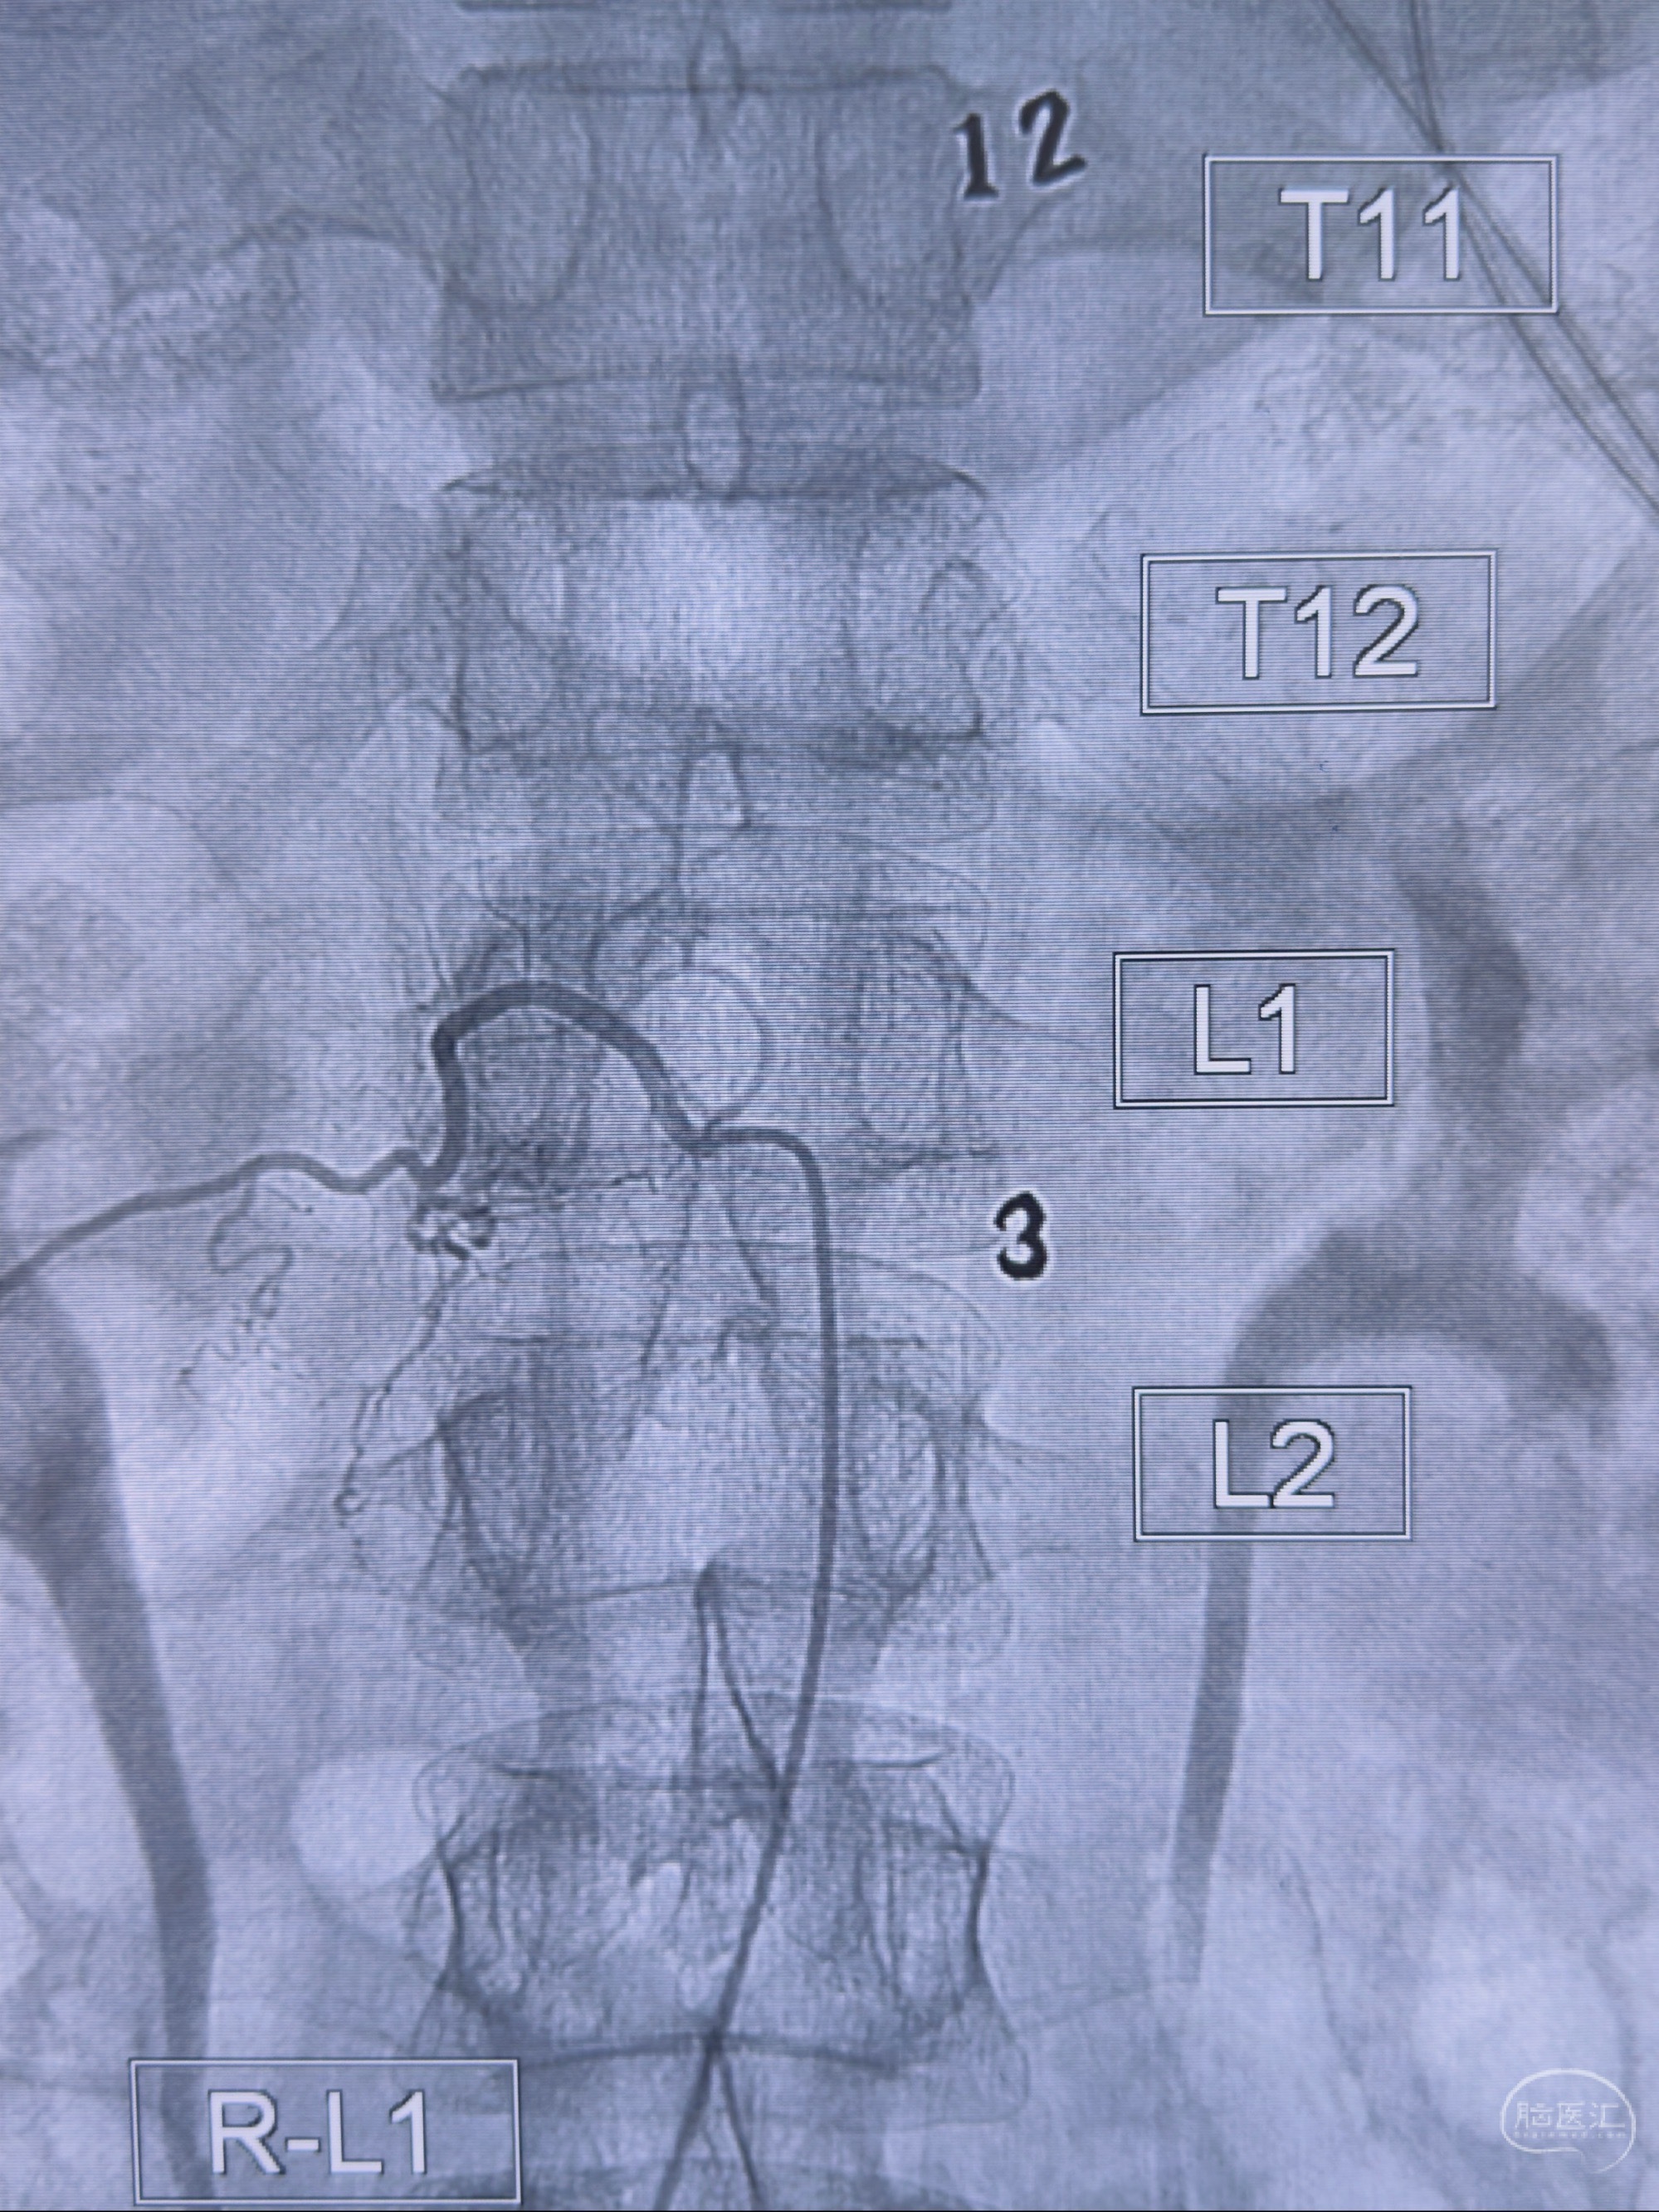

2023-10-13DSA:右侧L1水平硬脊膜动静脉瘘,供血动脉为右侧L1,附近动脉未见明确吻合供血,供血动脉处可见脊髓前动脉发出